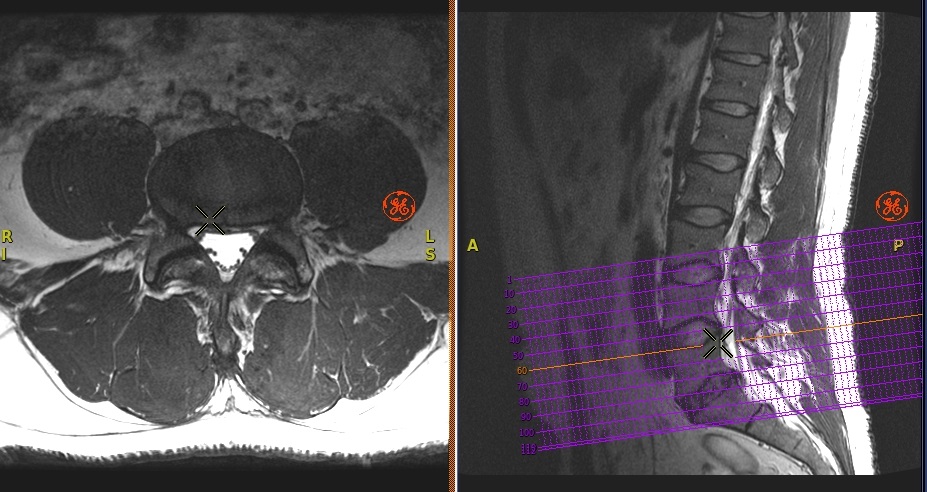

Figure 1. Cross-Reference image

An orange line represents the cross-referenced image location.